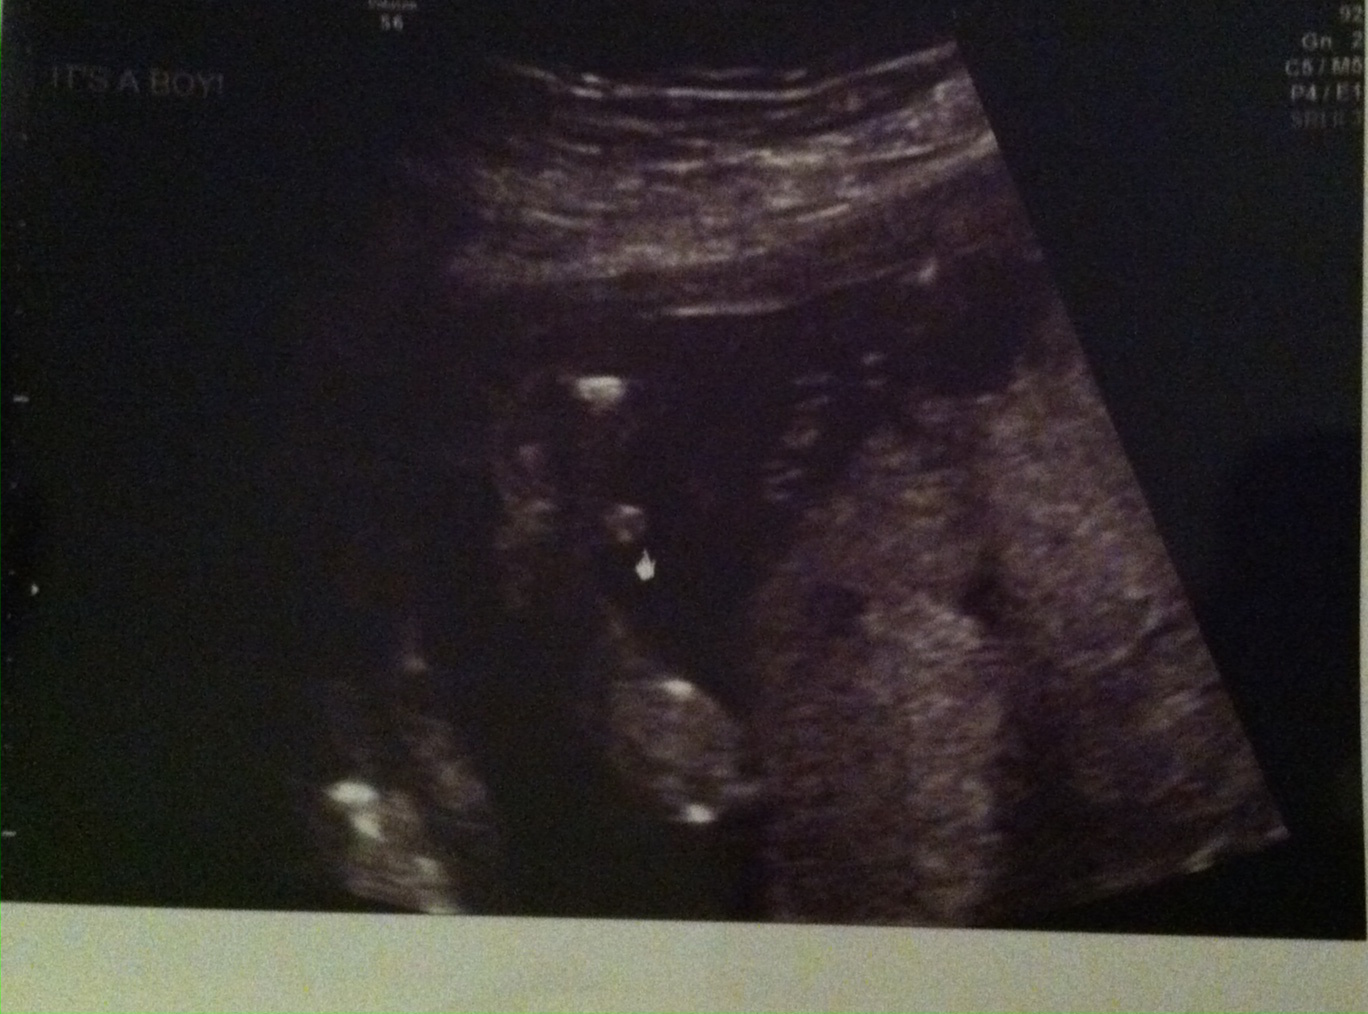

ITS A..................

Attachment 31623Attachment 31624BOY!

Thank you everybody for all your responses. This is my first child and I couldn't be any happier. Its what my husband and I wanted. Super thrilled can't wait for November to get here